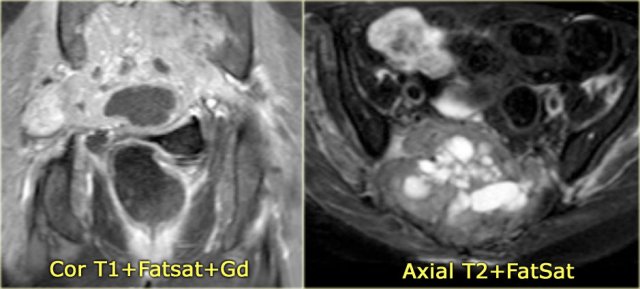

On the left a patient with a chondrosarcoma of the right acetabulum.

On the CT expansion and subtle calcifications are present.

On the coronal T2-weighted image the tumor is seen as a large lobulated mass with very high SI, which is typical for chondroid tumors.

The T1-weighted image after Gd shows typical peripheral nodular enhancement.

In the center there is no enhancement.

This is probably due to a large myxoid component. .